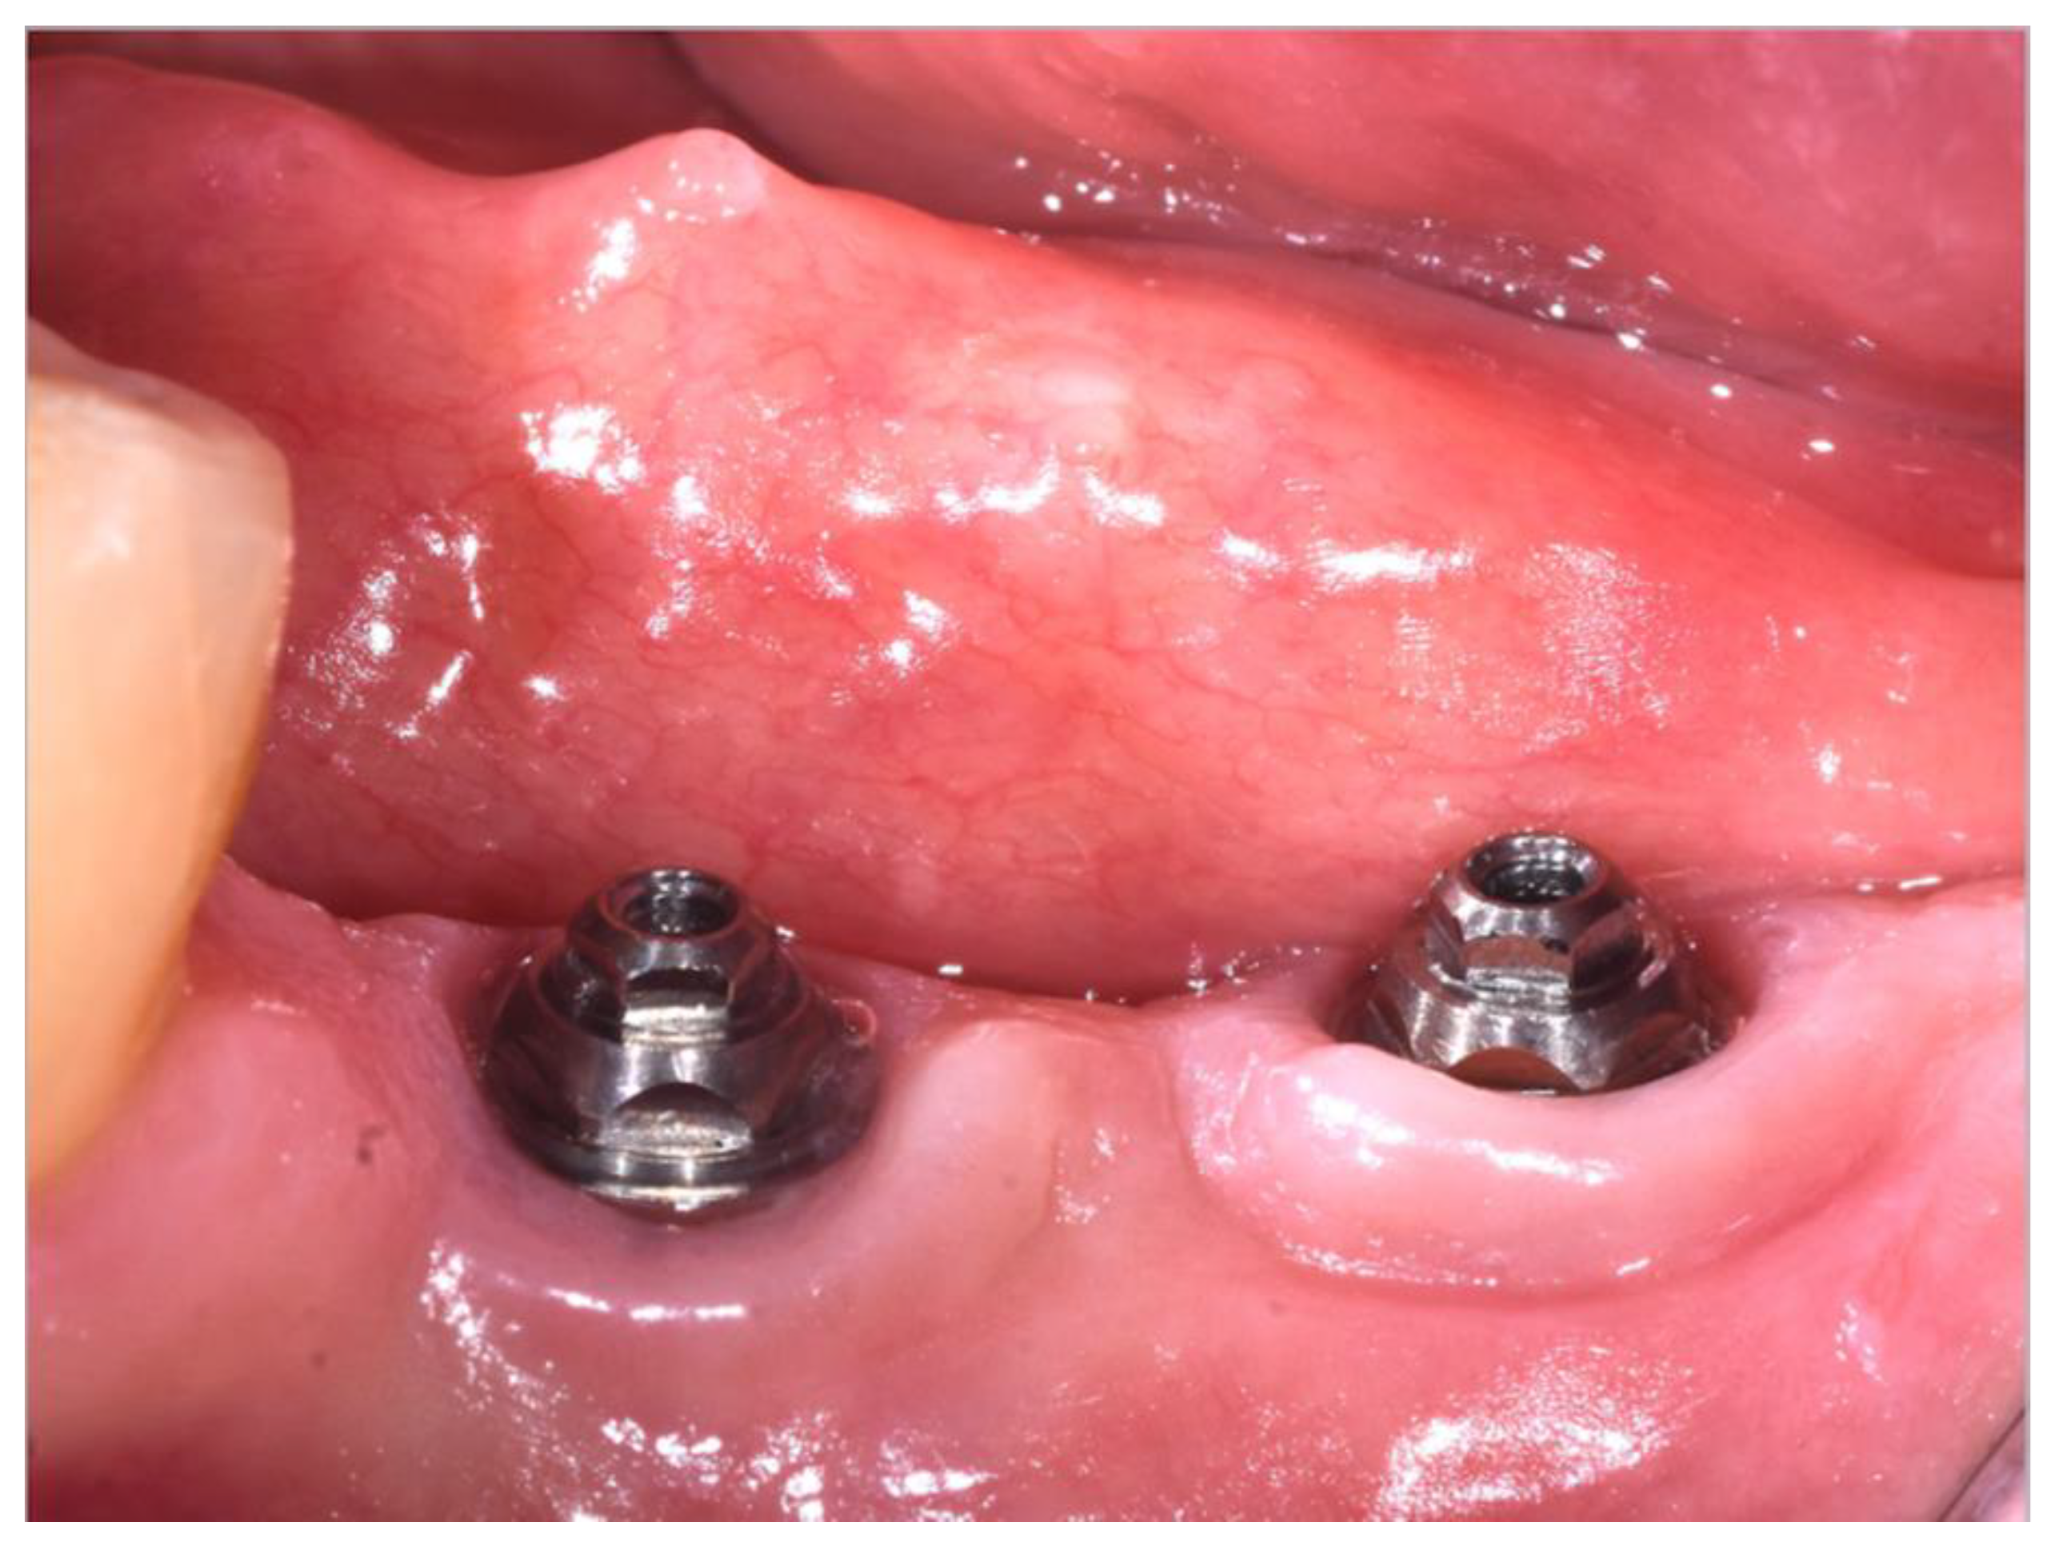

2.3. Surgical Appointments

- Peri-implant soft tissue parameters, including peri-implant probing depth (PPD), plaque index (PI), and bleeding index (BI). PPD was evaluated using a HuFriedy PCPUNC 15 probe (HuFriedy, Chicago, IL, USA) at the mesio-buccal, buccal, disto-buccal, mesio-lingual, lingual, and disto-lingual aspect of each implant. PI and BI were evaluated as number of surfaces (the mesio-buccal, buccal, disto-buccal, mesio-lingual, lingual, and disto-lingual) presenting plaque or bleeding on probing. All the parameters were evaluated at T6.